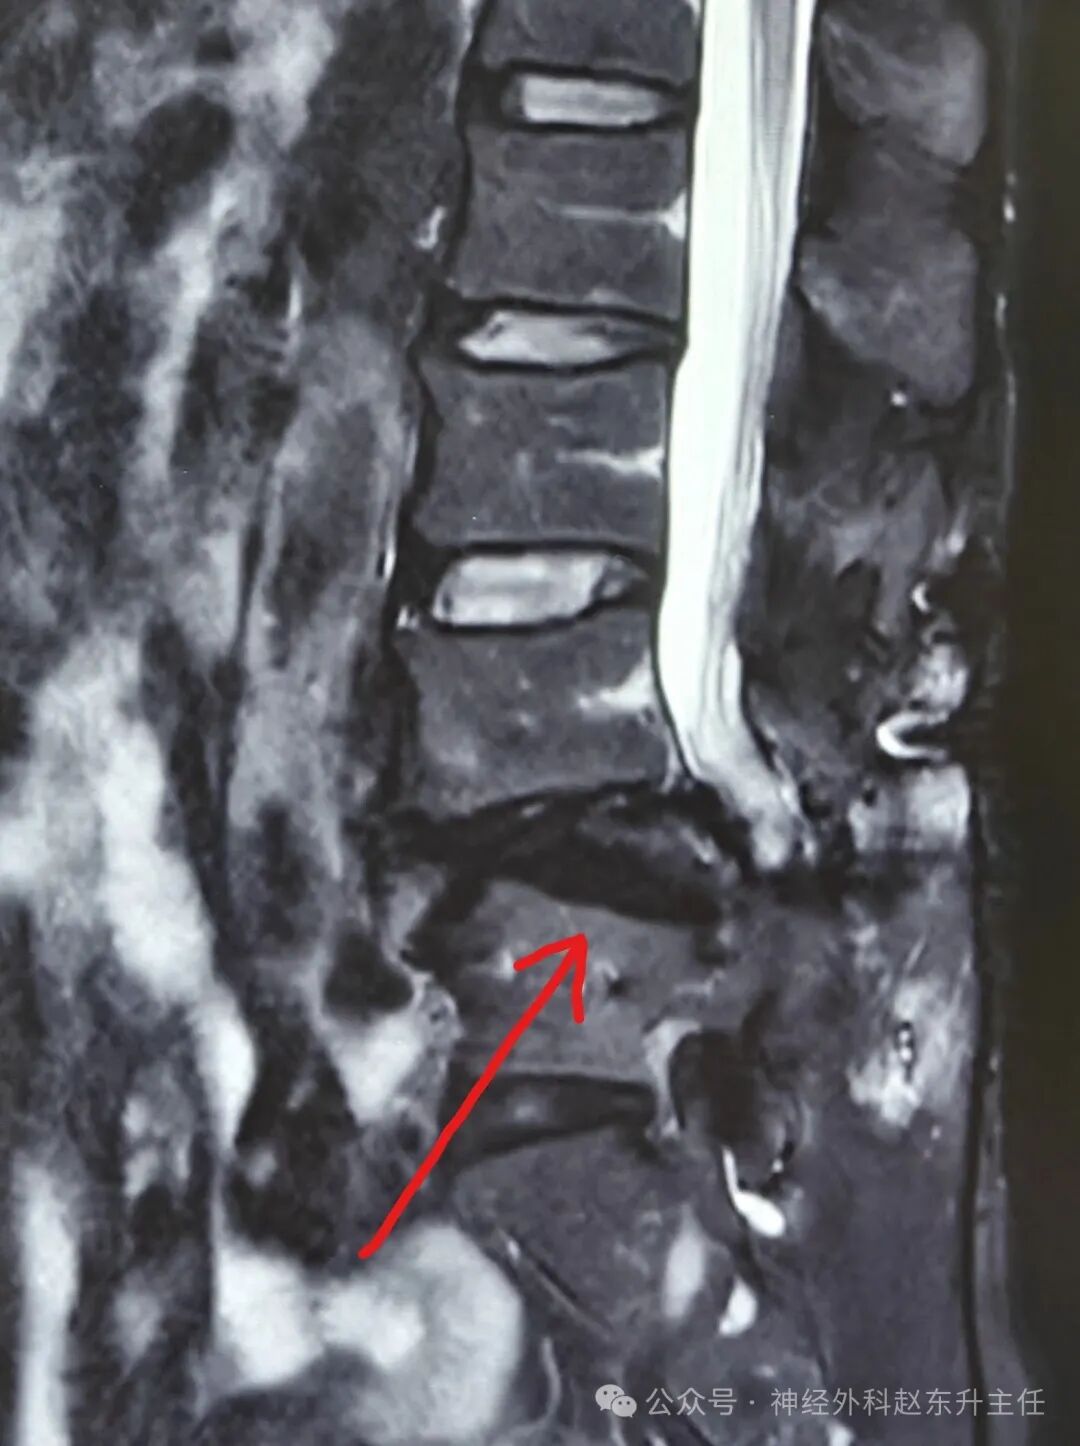

3.jpg腰椎MRI提示腰椎滑脱,马尾神经卡压